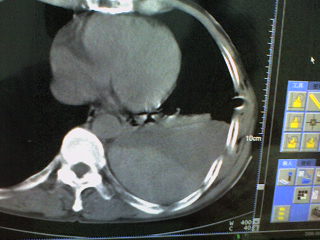

患者,男 51岁。突发性胸痛来诊。

起病急,症状重,应先除外心脏及大血管病变,左侧胸腔内可见囊实性病变,胸壁可见引流管影,建议提供完整的图像资料及相关的临床资料。

病变是胸腔内的。前部液体引出来的是血红色的液体。现在鉴别其后缘的高密度是什么?

这是一例胸膜外血肿形成的病例啊。。后面的高密度为凝血块。

手术证实的。